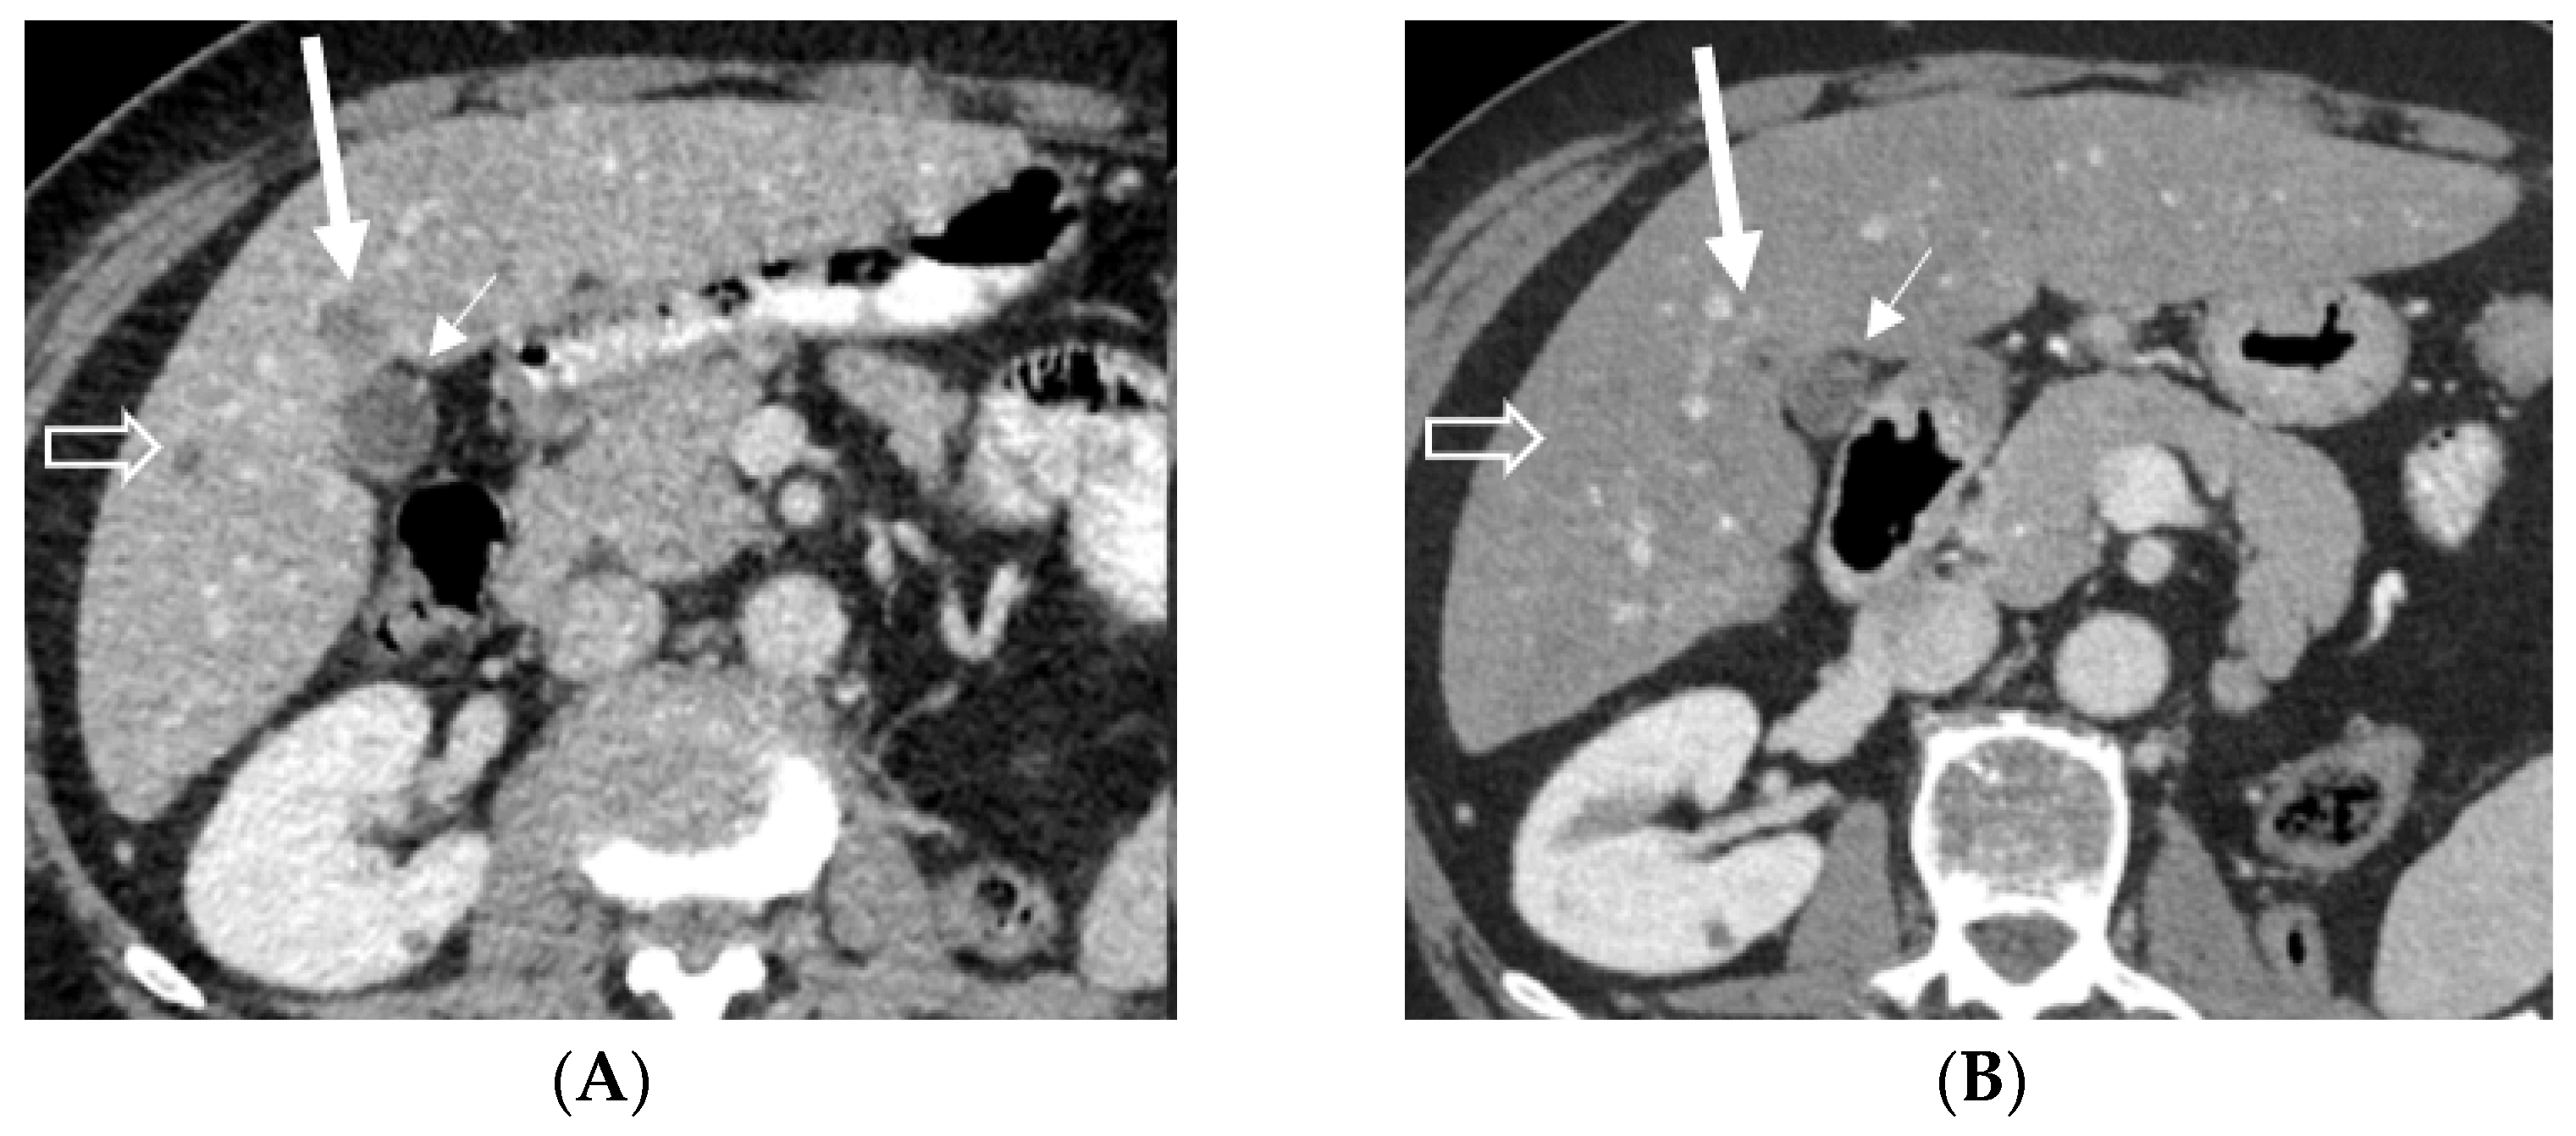

2.2. Case 2